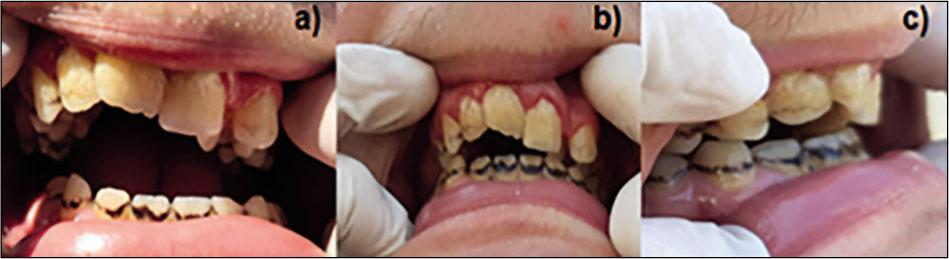

The child has downturned corners of the large mouth and a high-arched palate (Figure 3a).

At 16 years - dental examination was extremely difficult due to the mental handicap. Because of poor oral hygiene, multiple caries and residual roots are present, with marbling of the lower frontal incisors. He also presents enamel hypoplasia. The inflammatory periodontal index clearly indicates the presence of gingivitis (Figure 5).

Through correlation with the orthopantomography, the following aspects were highlighted (Figures 5, 6): the right superior central incisor insufficiently erupted, rotated mesially; both incisors with slight palatoversion; transposition between the left lateral incisor and canine. In addition, the patient has an open bite and the median line is deviated to the right. Supplementary, we found agenesis of third inferior molars on the orthopantomography (Figure 6).

Transposition between the left lateral incisor and canine (a) open bite (b) enamel hypoplasia and dental caries (c) at 16 years

There are studies claiming that dental manifestations such as delayed tooth eruption, bruxism, dental agenesis, especially oligodontia and micrognathia, cone-shaped teeth, enamel hypoplasia, worn teeth, dental attrition and discoloration of permanent dentition, as well as congenital taurodontism in the primary dentition, spacing, and over-retained misshapen primary molars, are the manifestations with variable expression in the clinical picture of the syndrome, possibly due to the extent and the specific locus of the chromosomal deletion [14, 23, 24, 25]. This patient presents some of these dental characteristics, such as delayed tooth eruption, bruxism, enamel hypoplasia, dental agenesis. Data from literature concluded that, in oligodontia, the main MSX1 gene placed at 4.9Mb of telomere [26, 27, 9], and other genes located outside the critical region, can be involved in this anomaly [25] because oligodontia has also been found in patients with deletions smaller than 2.7 Mb [7,25].